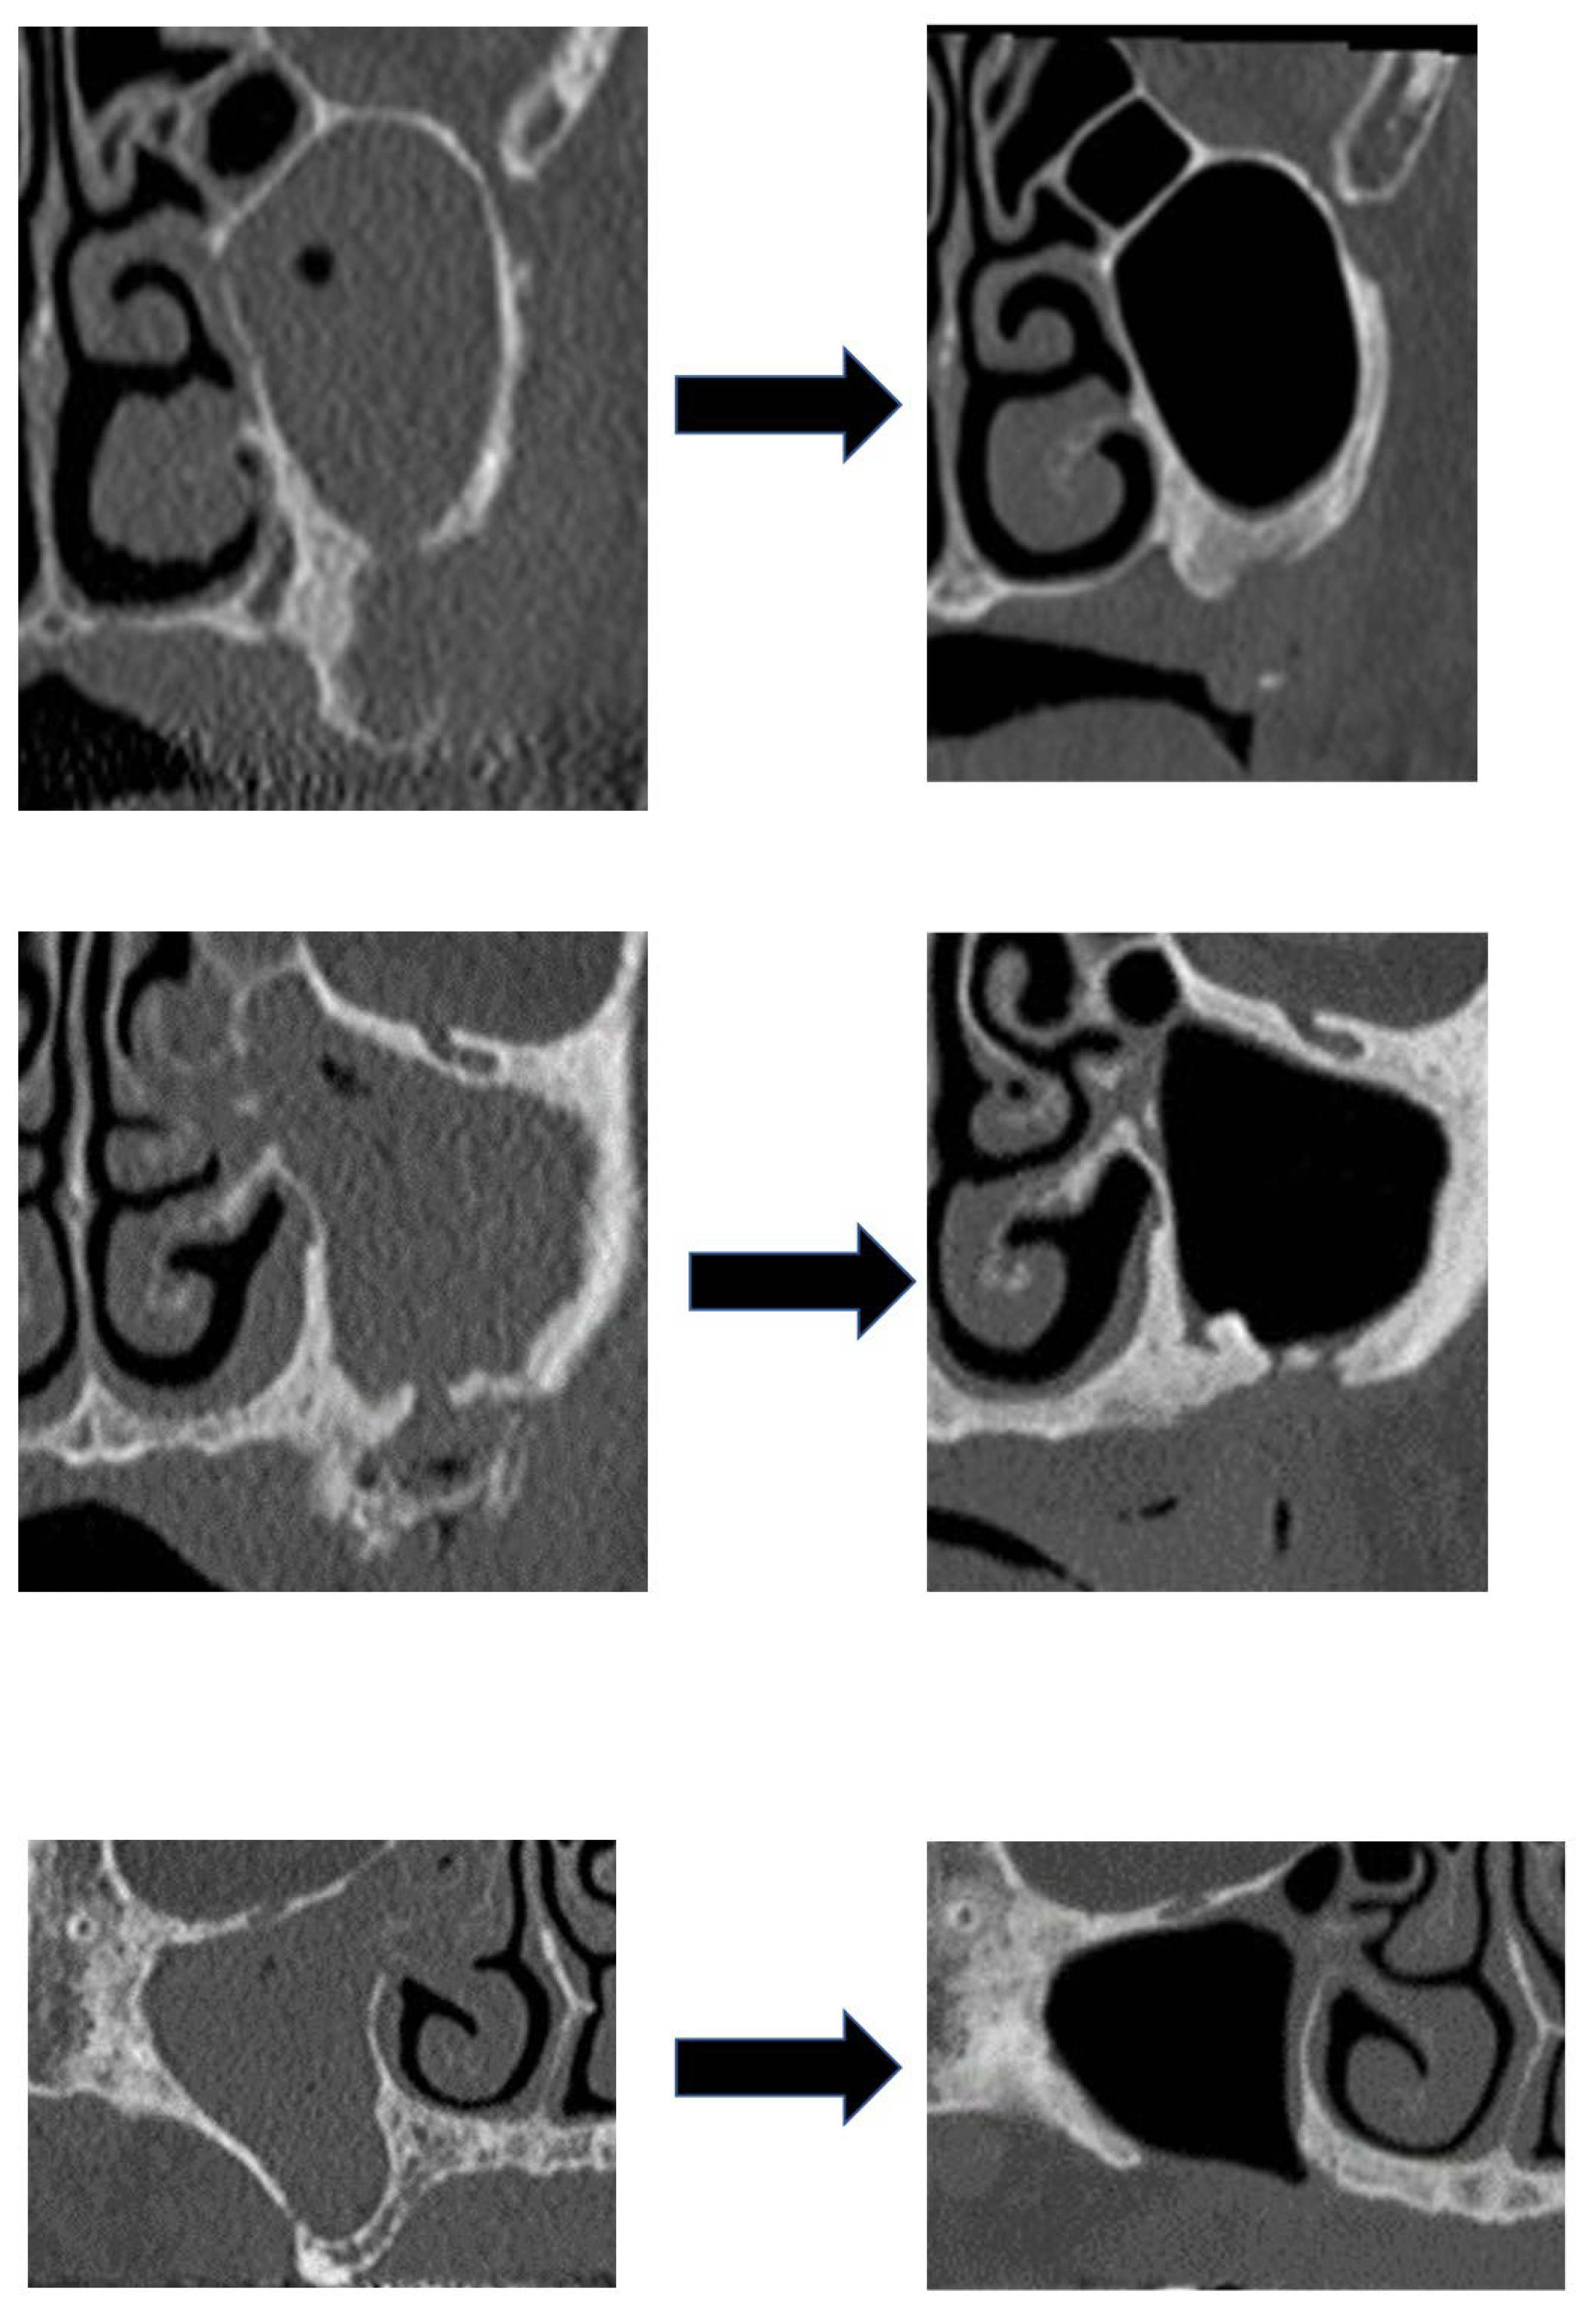

| Procedures for Maxillary Sinus | Grade of Maxillary Sinusitis | Total | |||

|---|---|---|---|---|---|

| Grade 1 | Grade 2 | Grade 3 | Grade 4 | ||

| None | 7 | 6 | 1 | 7 | 21 |

| Intraoperative irrigation | 0 | 3 | 0 | 10 | 13 |

| Total | 7 | 9 | 1 | 17 | 34 |